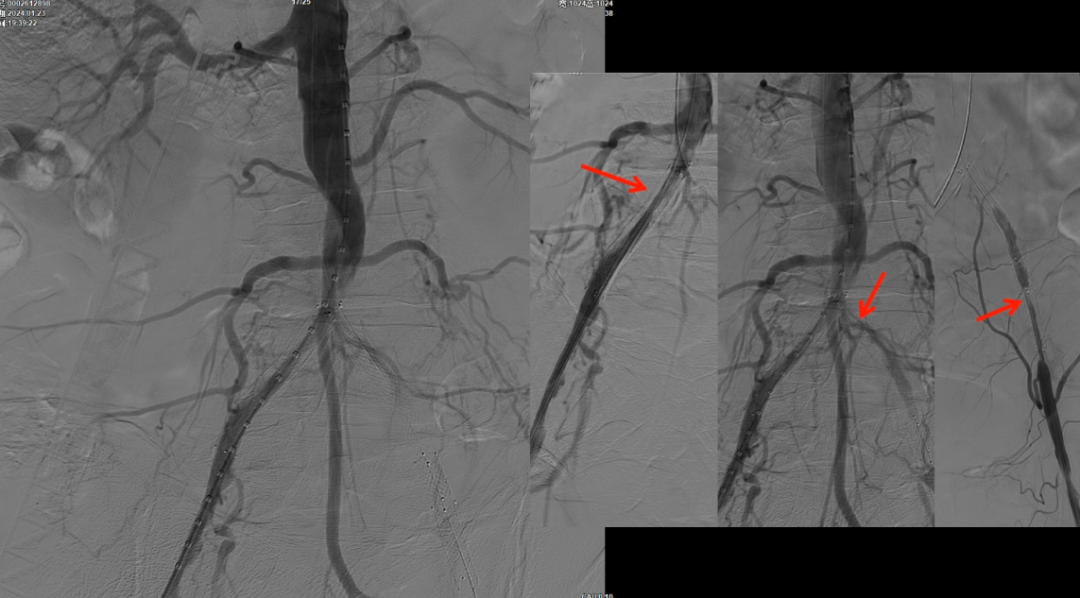

减容后造影显示仍存在重度残存狭窄,遂沿右侧股动脉置入VBX支架(直径11mm,长度59mm)。支架定位需满足近端完全覆盖腹主动脉病变段,远端距离双侧髂总动脉分叉至少1.5cm,以避免后扩张时大球囊对髂动脉造成损伤。

CERAB技术的关键点一:经双侧股总动脉植入2枚VBX球囊扩张式覆膜支架(8L×79mm),与腹主动脉覆膜支架腔内平行放置,且两枚支架端平齐对接。

CERAB技术关键点二:先用14mm×40mm球囊分别扩张双侧髂肢的腹主动脉段。

再用8mm球囊对双侧髂支腹主动脉段行对吻扩张,以确保双侧髂支与腹主动脉覆膜支架腔内获得良好的贴壁形态,最大程度减少空腔,降低远期再狭窄发生率。

右侧髂外动脉存在残存狭窄,因该部位无原有裸支架覆盖,为节省治疗费用,选择植入1枚直径8mm的裸支架,并采用8mm球囊进行后扩张。

即时效果:造影显示腹主动脉、双侧髂总/髂外动脉及股动脉通畅。